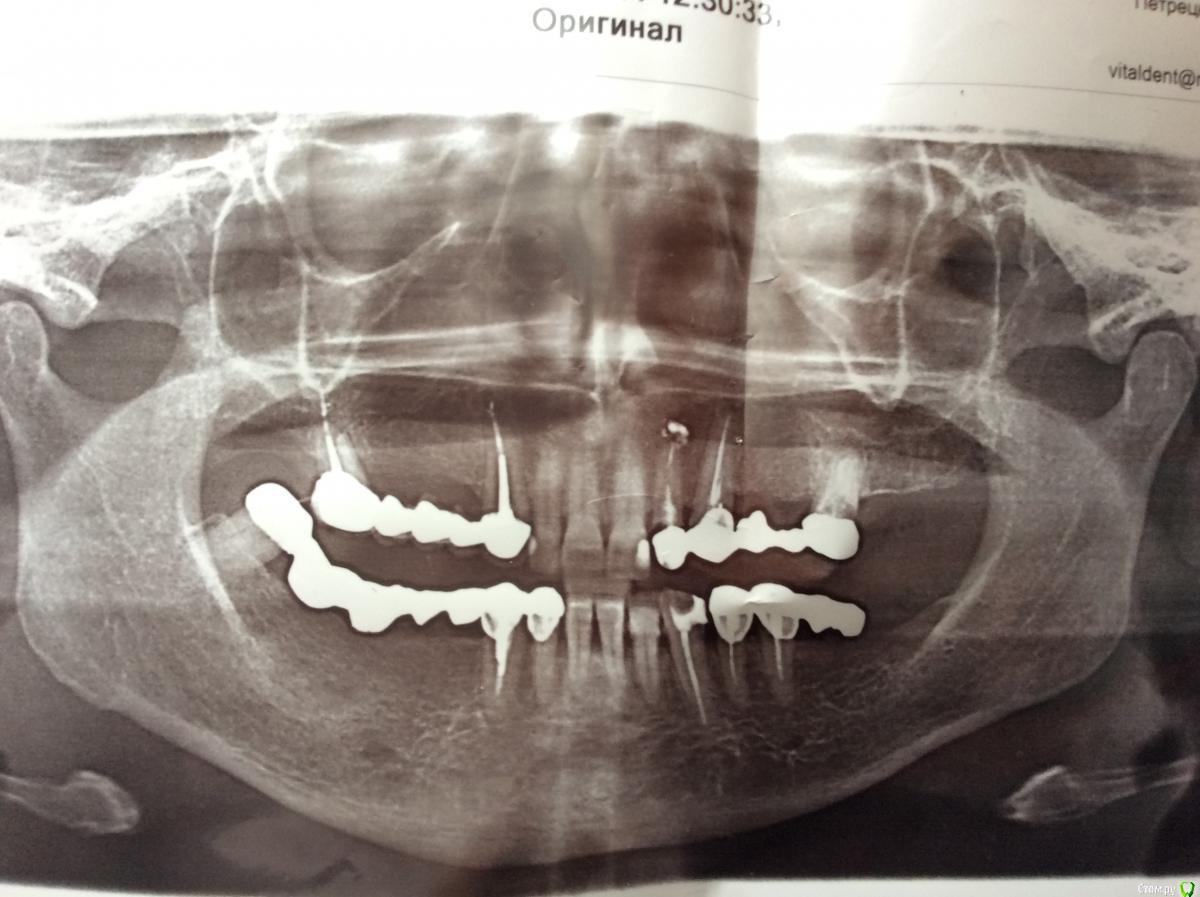

dr.Dre Опубликовано 18 июня, 2017 Поделиться Опубликовано 18 июня, 2017 Добрый день уважаемые коллеги,пациентка обратилась с жалобами на боли в 48,и замену мк снизу.Стоит ли вскрывать данный зуб или сразу на удаление ? Ссылка на комментарий

Асхат Опубликовано 18 июня, 2017 Поделиться Опубликовано 18 июня, 2017 если есть возможность у пациентки на имплантацию , то снять мост установить 4 или хотя бы 3 импланта и удалить 48, если нет то попробовать пролечить через коронку и пусть стоит сколько протянет, объяснить что это не надолго и пусть морально и финансово готовится к имплантам, а переделывать мост думаю нестоит Ссылка на комментарий

parallax Опубликовано 18 июня, 2017 Поделиться Опубликовано 18 июня, 2017 А 48 подвижен? Налицо функциональная перегрузка. Ссылка на комментарий

dr.Dre Опубликовано 18 июня, 2017 Автор Поделиться Опубликовано 18 июня, 2017 А 48 подвижен? Налицо функциональная перегрузка.1 степень подвижности Ссылка на комментарий

parallax Опубликовано 18 июня, 2017 Поделиться Опубликовано 18 июня, 2017 Тогда вскрывайте, лечите. Не удалять же. Без гарантий и под ответственность пациента. А потом ЧСПП. Ссылка на комментарий

dr.Dre Опубликовано 18 июня, 2017 Автор Поделиться Опубликовано 18 июня, 2017 Тогда вскрывайте, лечите. Не удалять же. Без гарантий и под ответственность пациента. А потом ЧСПП.допустим сделаю ендо,как думаете сколько он может простоять с такой окклюзионной нагрузкой? Ссылка на комментарий

AndyAndy Опубликовано 18 июня, 2017 Поделиться Опубликовано 18 июня, 2017 Вы хотите мост сделать, такой же как на снимке? Этот зуб раскачается очень быстро и вам предъявят что: я ходила со штамповкой 10 лет и все было ок, а вы мне поставили мк за бешеные деньги и через год опять снимать??? Удалять конечно, для чспп он тоже не нужен Ссылка на комментарий